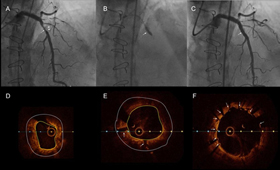

圖二、 A. 冠狀動脈血管攝影顯示左前降支的狹窄區域(箭頭)及周圍鈣化斑塊(三角形)。B. 使用震波球囊導管於鈣化區域進行震波碎石術(箭頭所示)。C. 震波碎石術後,狹窄的血管完全擴張,並成功放置支架,冠狀動脈攝影顯示病灶明顯改善(箭頭所示)。D. 冠狀動脈光學斷層掃描顯示病變區域的環狀鈣化(黃與白色圈之間),測量病灶血管內徑約為2mm。E.震波碎石術後,鈣化區域出現裂縫(箭頭所示),使後續使用氣球導管更容易擴張病灶。F.支架放置後的冠狀動脈光學斷層掃描顯示支架緊貼血管壁(箭頭所示),測量病灶血管內徑約為4mm,獲得顯著改善。